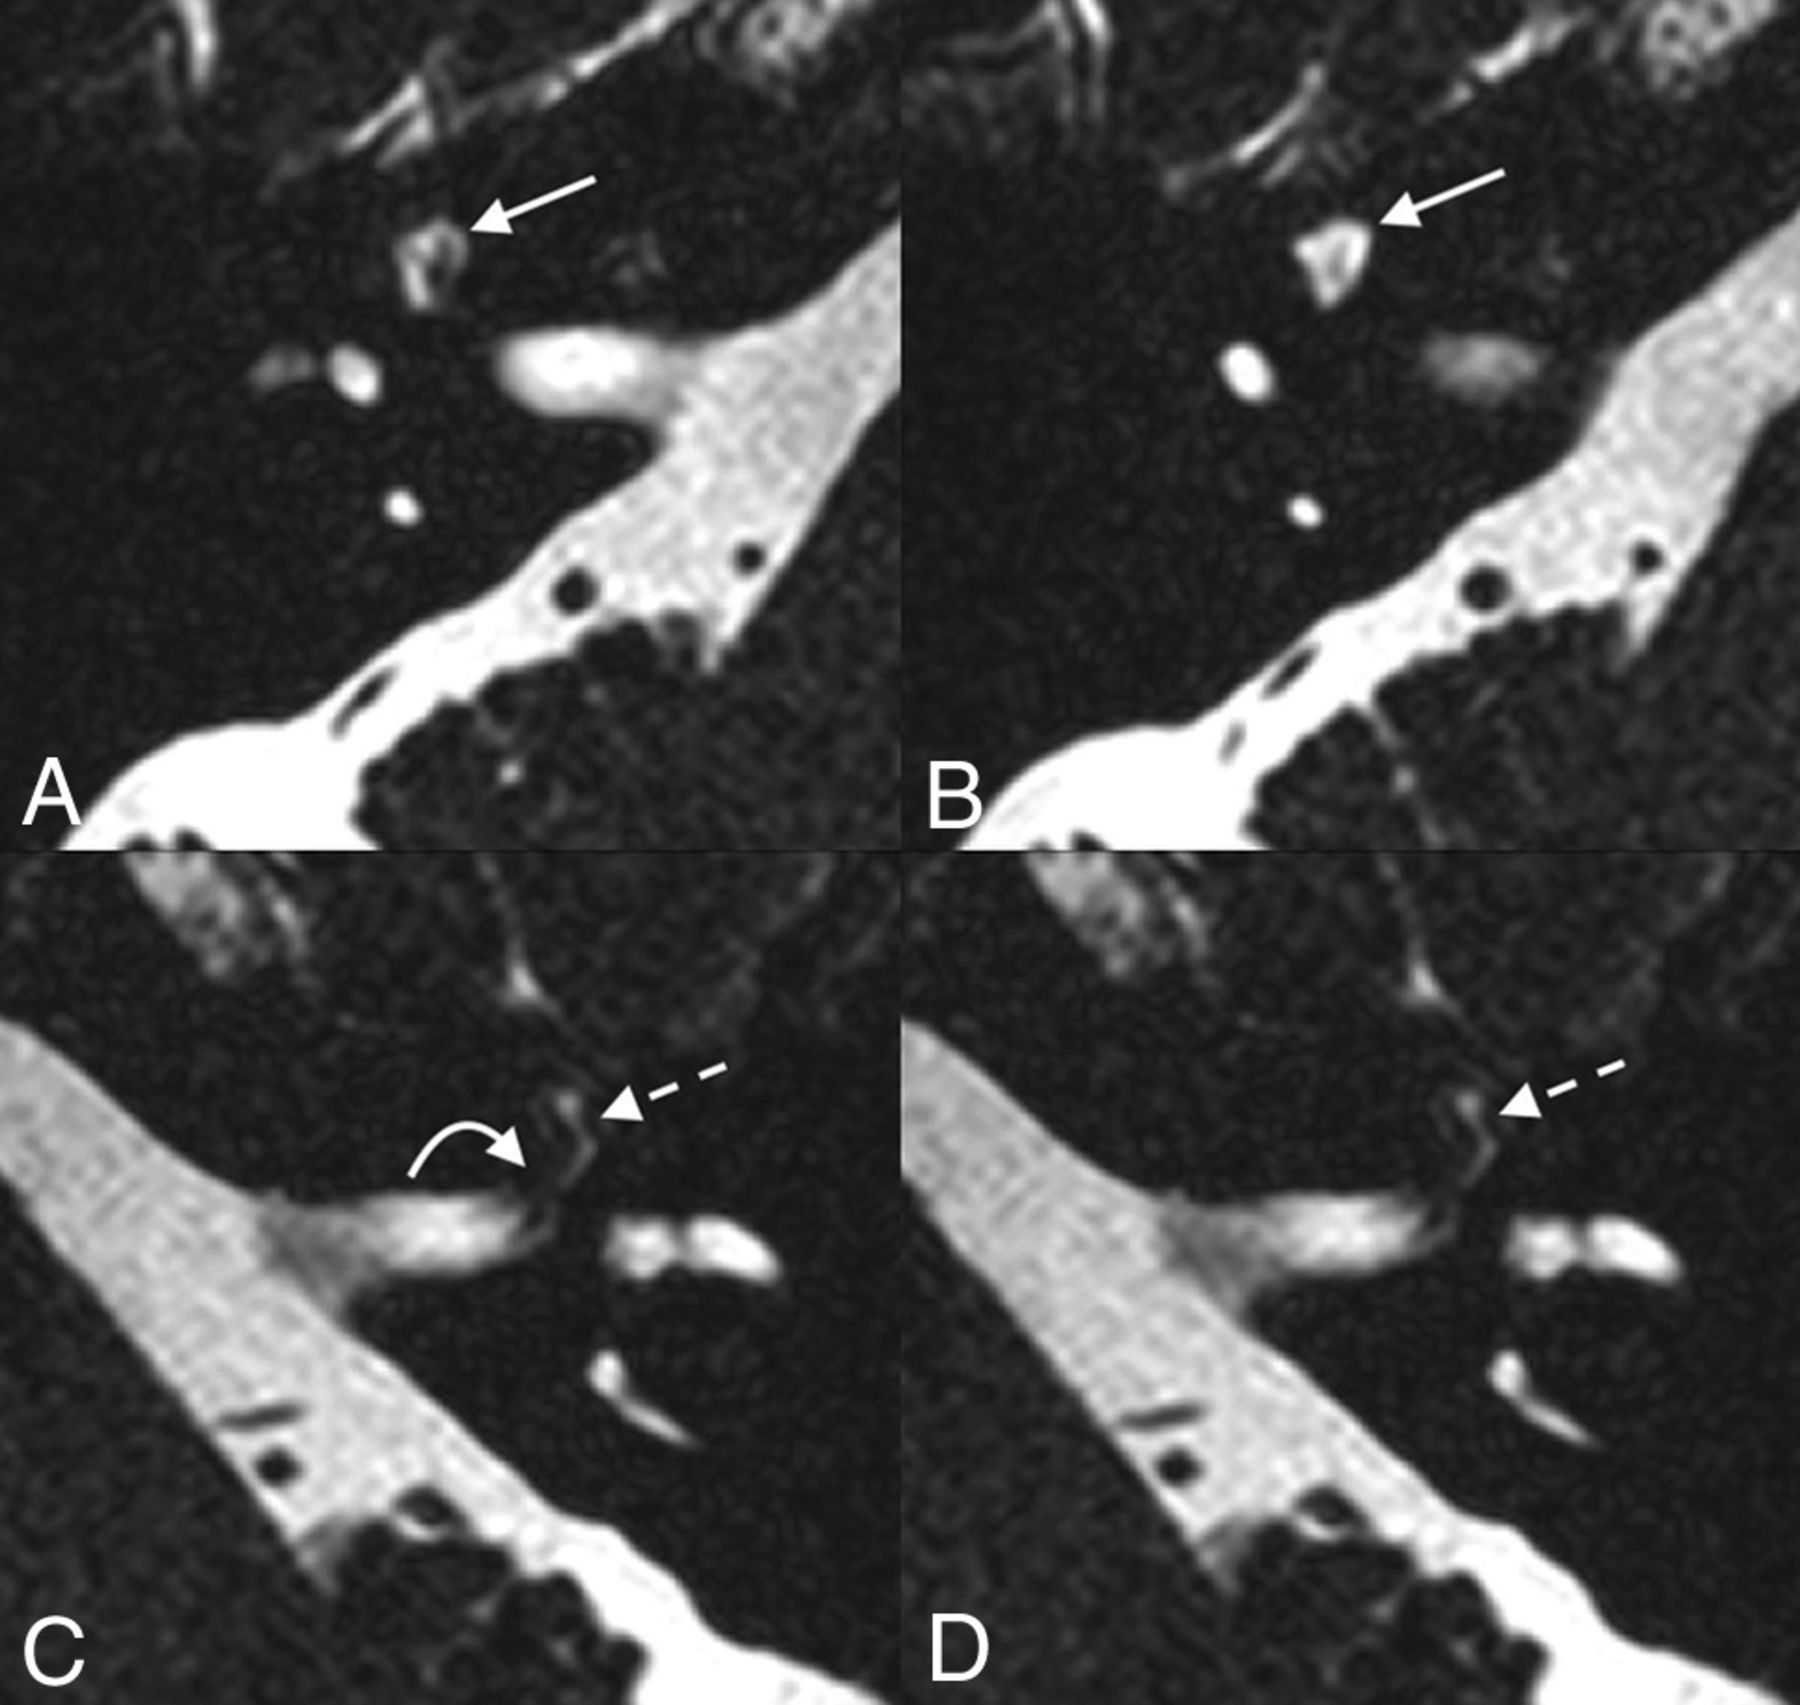

A 64-year-old woman who presented with bilateral sensorineural hearing loss. Axial T2 SPACE imaging demonstrates fluid-filled dilation of the right geniculate ganglion fossa, compatible with a meningocele (solid straight arrow, A and B). Fluid is seen in the left labyrinthine (curved arrow, C) and geniculate (dashed straight arrow, C and D) segments of the left facial nerve canal without remodeling/dilation of the osseous canal.